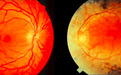

正常视网膜(左)和 RP 视网膜(右)的对比,后者为经典三联征 视网膜血管变细、视盘蜡样苍白及视网膜内骨针样色素沉着